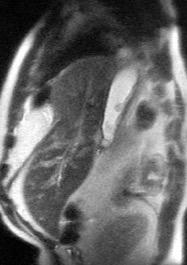

Hallazgos en RM .

Buena en casos dudosos

Cortes sagitales y coronales: Interrupción de la línea diafragmática

Paciente que ingresa con síntomas de colecistitis aguda. Antecedentes de trauma importante muchos años antes

Zhao L et al. Delayed traumatic diaphragmatic rupture: diagnosis and surgical treatment. © Journal of Thoracic Disease.

J Thorac Dis 2021

Asas

Líquido pericolecistítico

V. biliar con cálculos

Diafragma